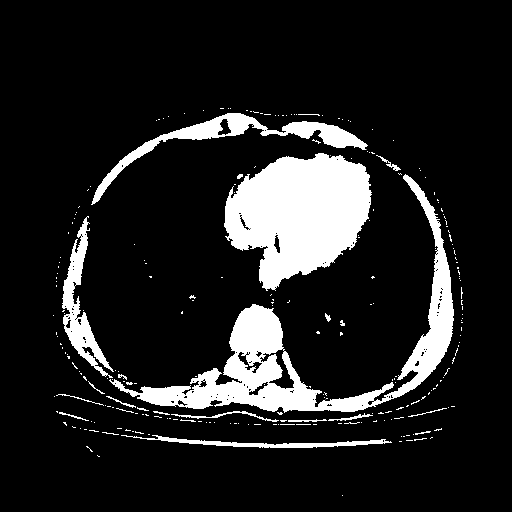

Image Grid

4Γ—3 grid: Rows show different image types (Original NATIVE, Reconstructed NATIVE, Original VENOUS, Generated VENOUS), Columns show windowing techniques (No Window, Lung Window, Mediastinum Window)

Reconstructed NATIVE CT scan (cycle consistency)

Full window (WL 1023.5, WW 4095 β†’ Low βˆ’1024, High +3071)

Actual HU range: [-1024.0, 3071.0]